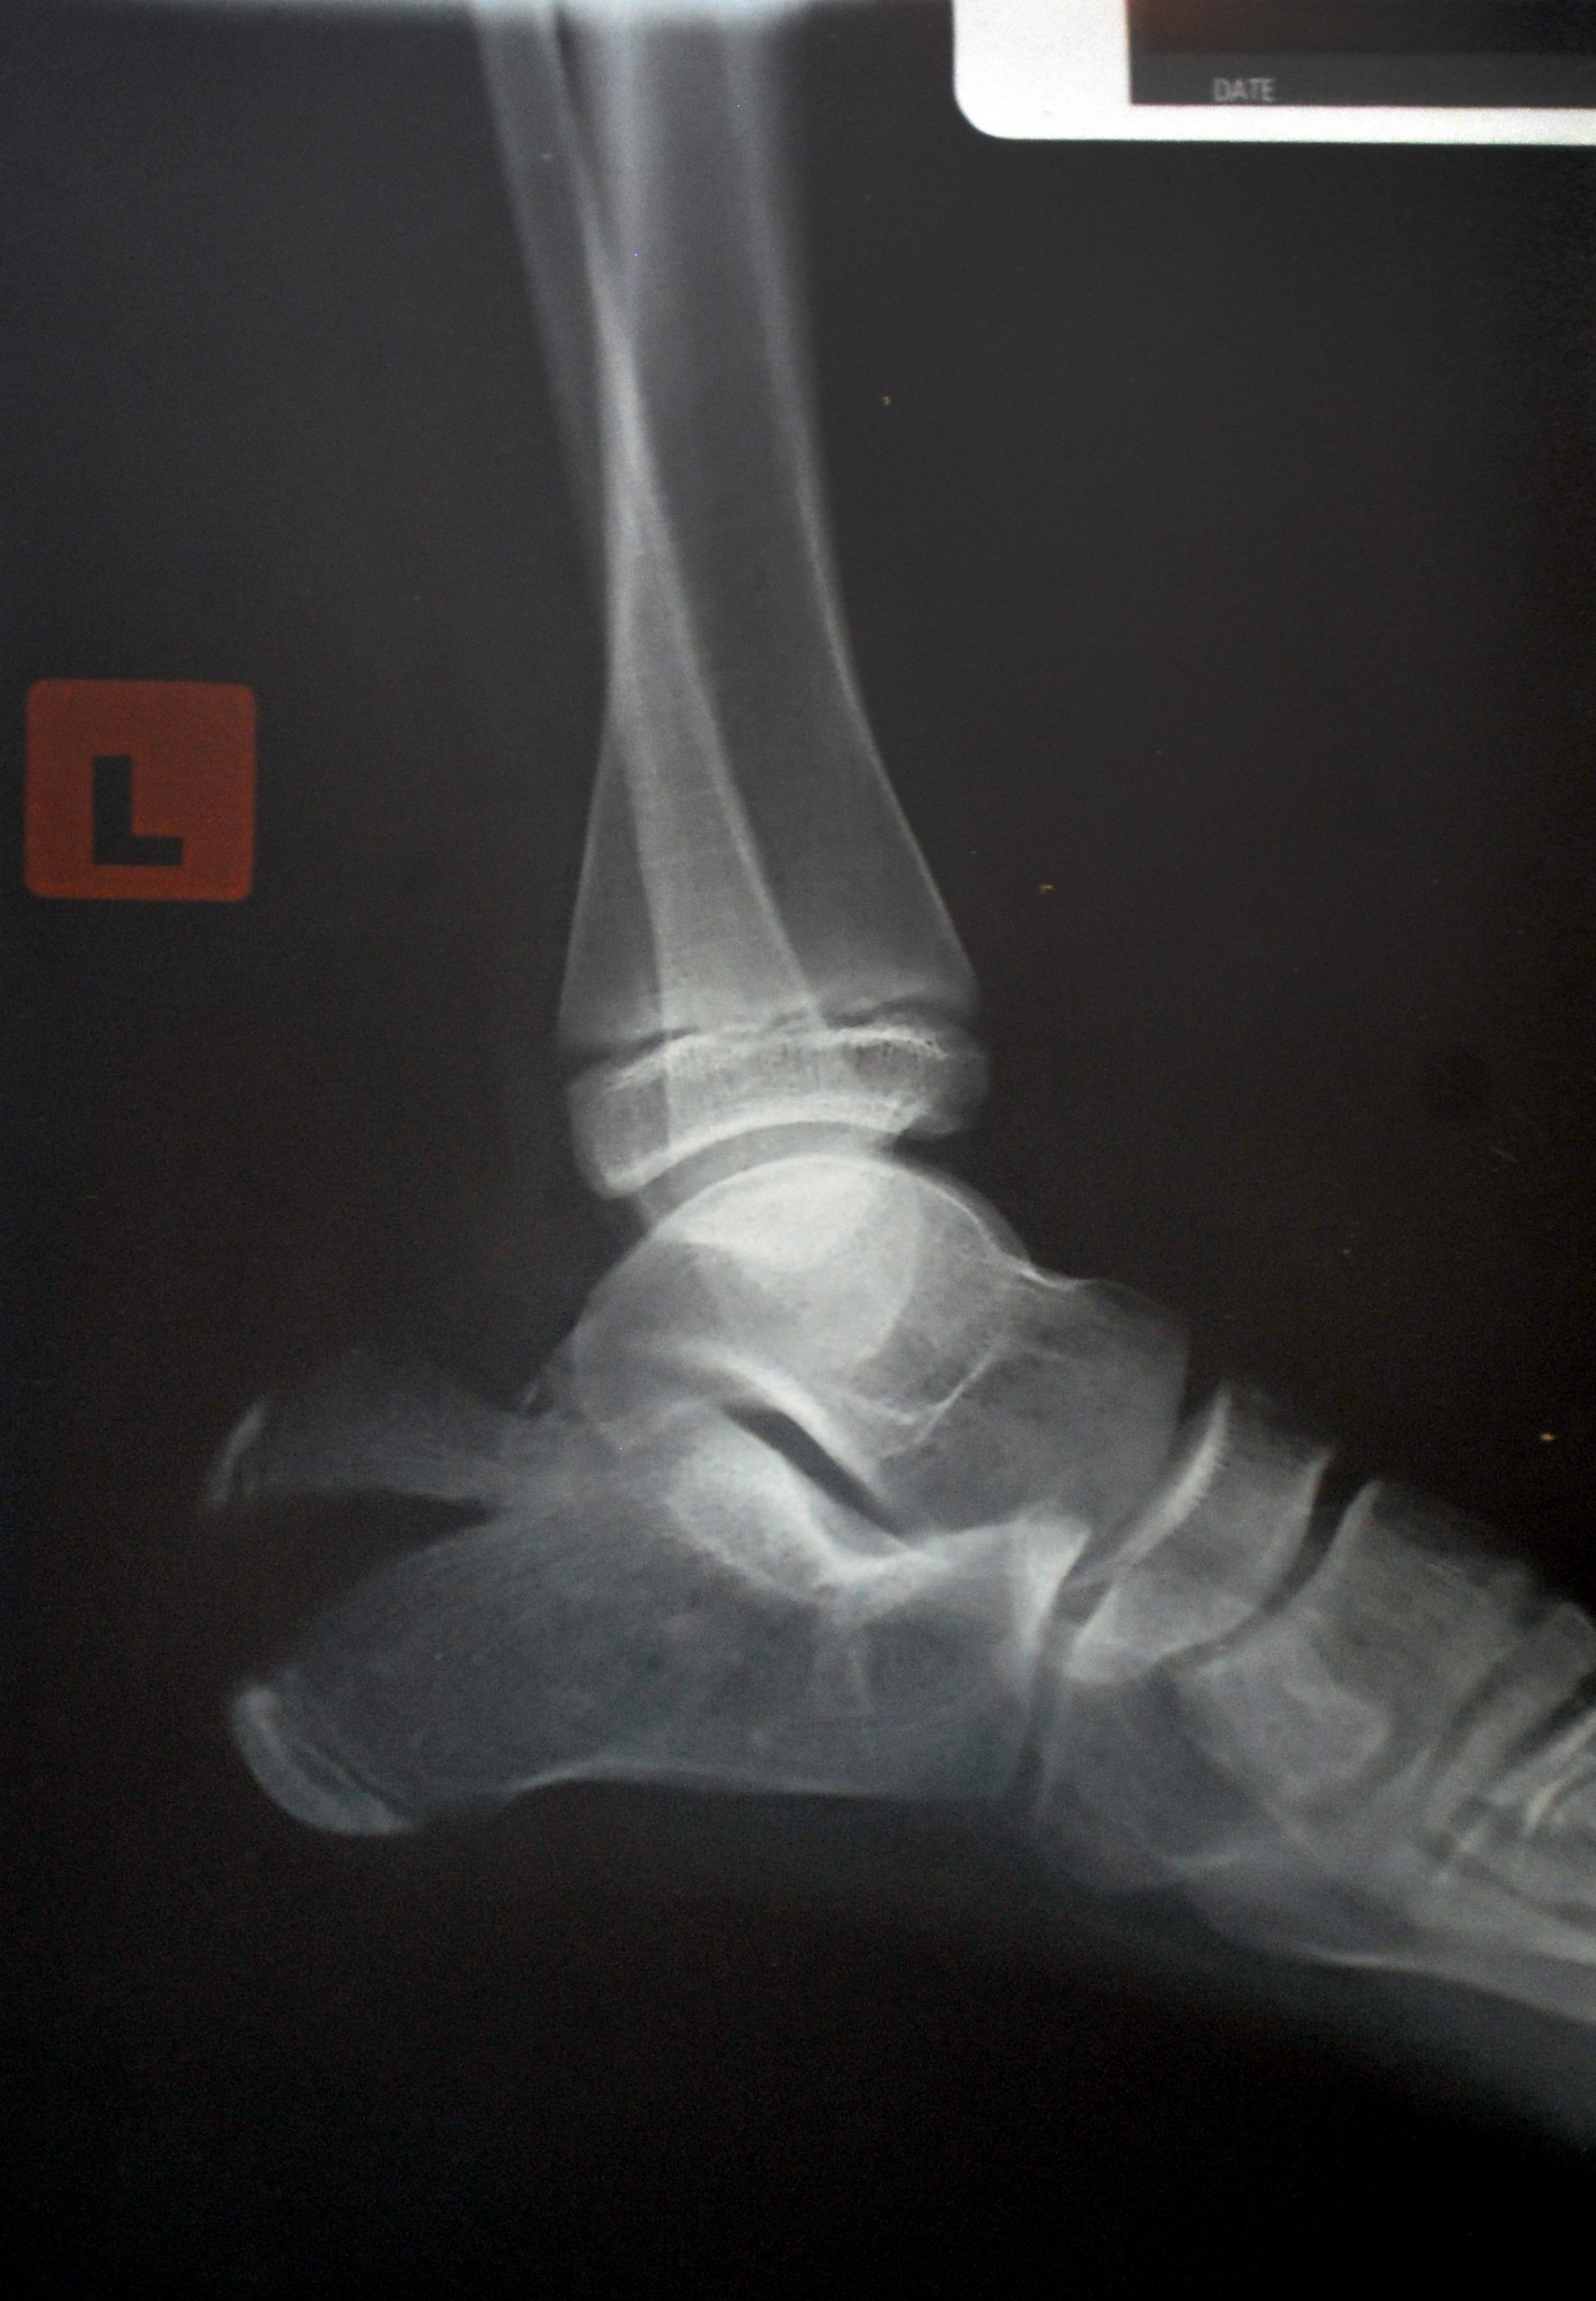

Sam Castelow, who has osteogenesis imperfecta type one, entered in the mentally and physically draining Tough Mudder at Phillip Island to raise awareness and money for the OI Foundation.

The 24 year-old has had eight major broken bones in her life and several other smaller injuries.